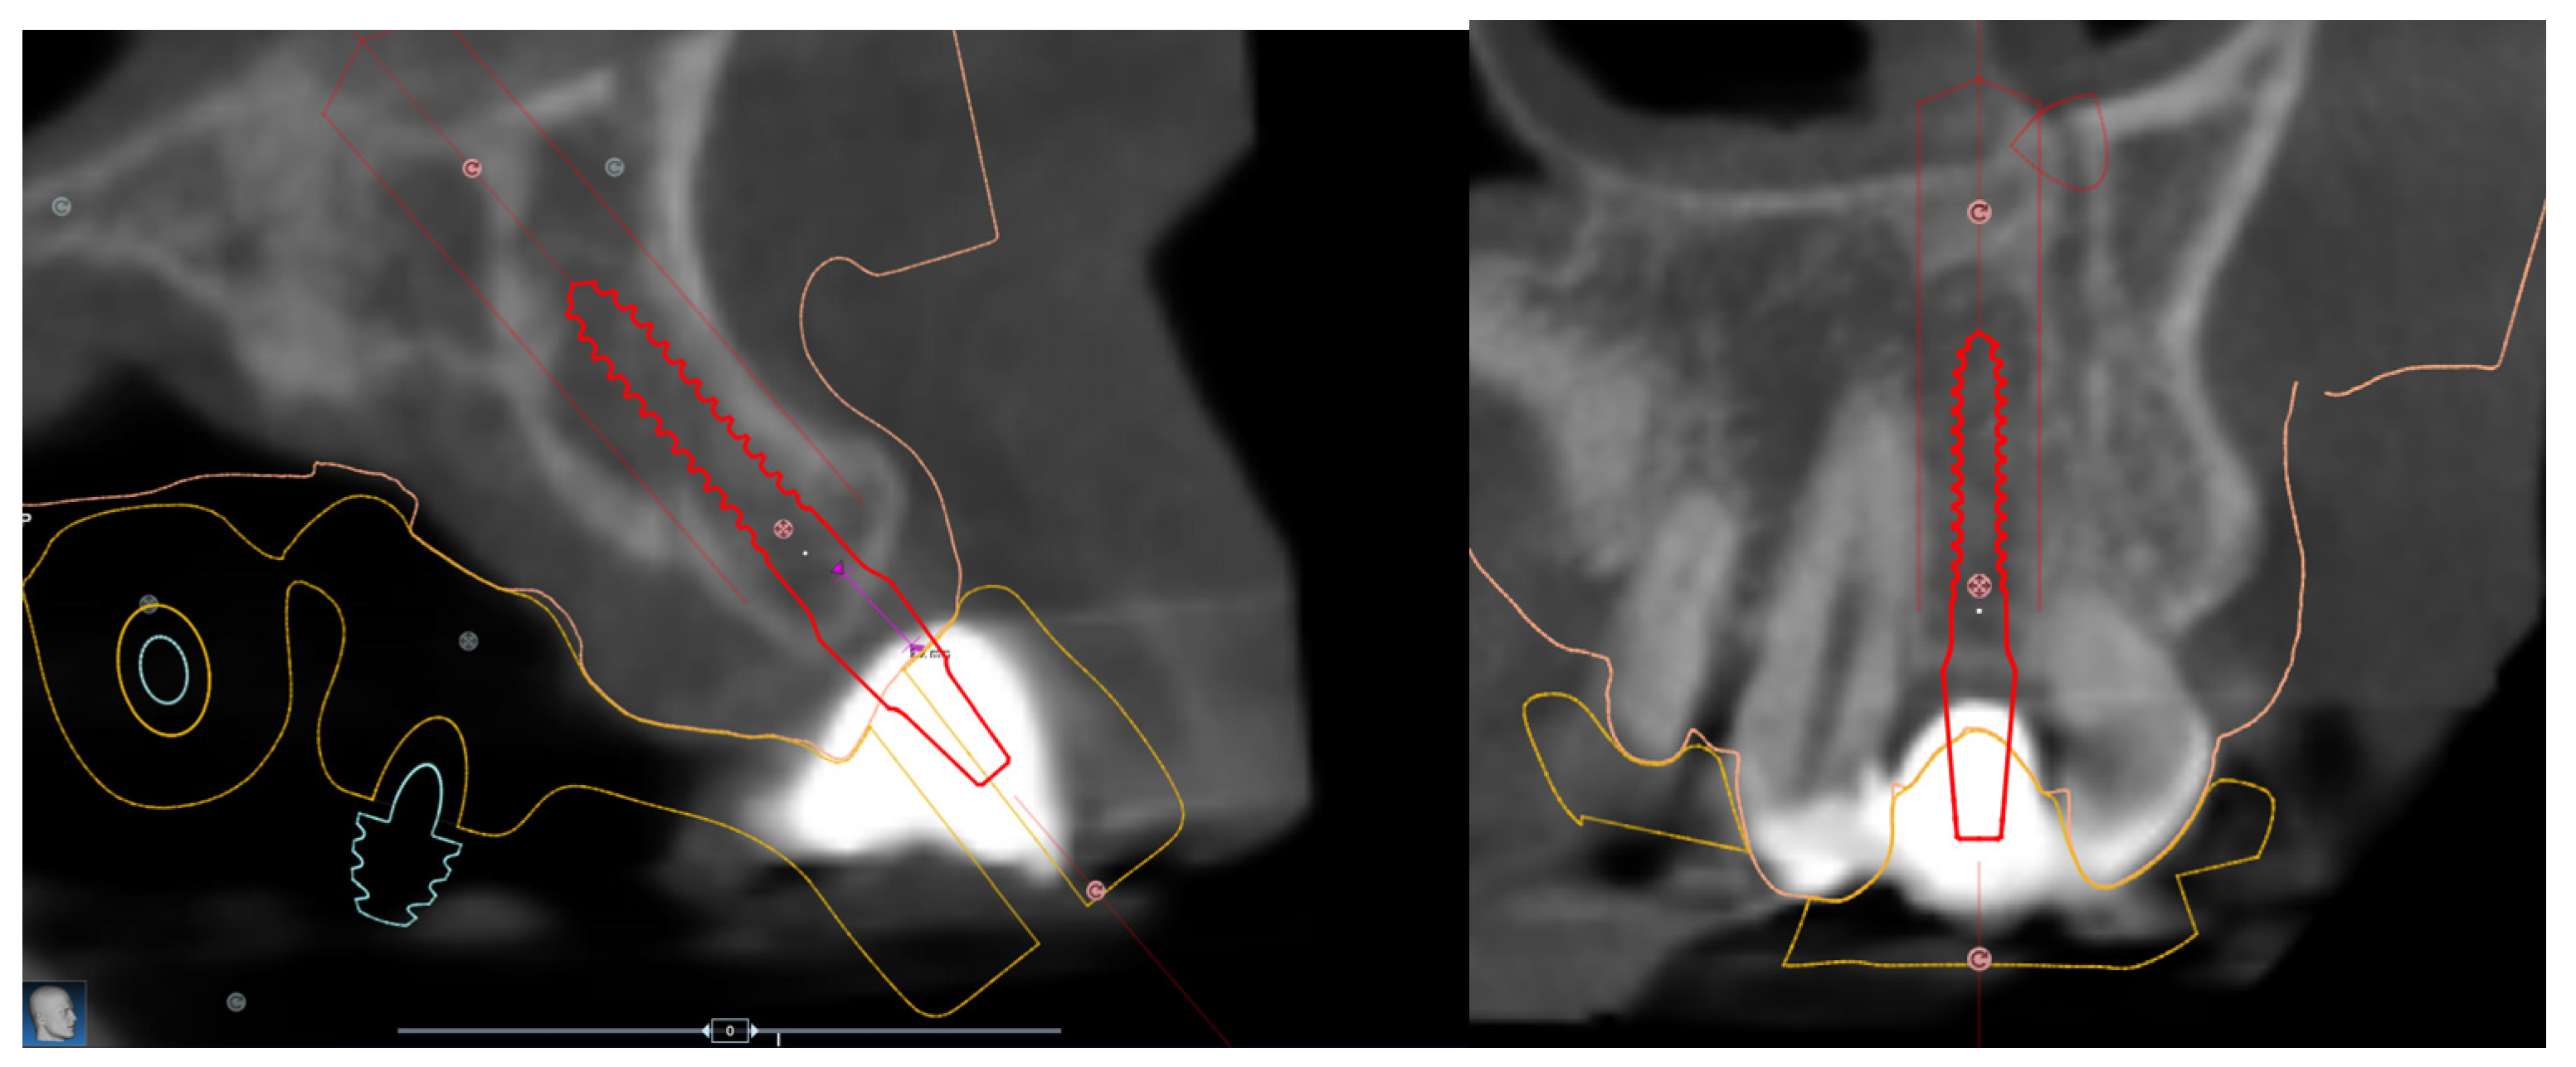

2.2. Surgical Protocol

2.3. Prosthetic Protocol